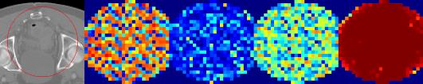

Evaluating lesion progression and treatment response via longitudinal lesion tracking plays a critical role in clinical practice. Automated approaches for this task are motivated by prohibitive labor costs and time consumption when lesion matching is done manually. Previous methods typically lack the integration of local and global information. In this work, we propose a transformer-based approach, termed Transformer Lesion Tracker (TLT). Specifically, we design a Cross Attention-based Transformer (CAT) to capture and combine both global and local information to enhance feature extraction. We also develop a Registration-based Anatomical Attention Module (RAAM) to introduce anatomical information to CAT so that it can focus on useful feature knowledge. A Sparse Selection Strategy (SSS) is presented for selecting features and reducing memory footprint in Transformer training. In addition, we use a global regression to further improve model performance. We conduct experiments on a public dataset to show the superiority of our method and find that our model performance has improved the average Euclidean center error by at least 14.3% (6mm vs. 7mm) compared with the state-of-the-art (SOTA). Code is available at https://github.com/TangWen920812/TLT.